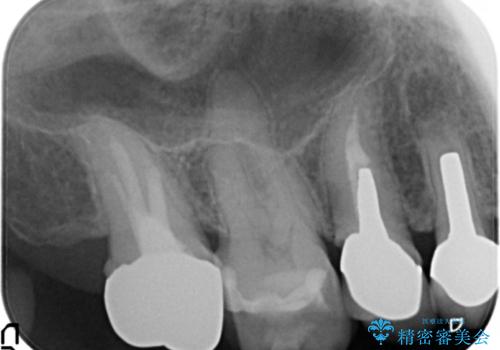

臼歯部メタルフリー再補綴

- 治療してからの年月が経過し、かみにくくなったブリッジ・クラウンを全てやりかえたいと希望され来院されました。

クラウン・ブリッジを作り替えるにあたり虫歯の徹底的な除去・根管治療のやり直しを行い今後やり直しをしなくて済むような環境を整えていきます。

装着して長期間経過したブリッジやクラウンは隙間から細菌が侵入し虫歯が再発してしまっていることがあります。

長期的に問題のないブリッジ・クラウンを作製するため、虫歯をしっかりと除去すること精密な根管治療を行うことが肝要です。